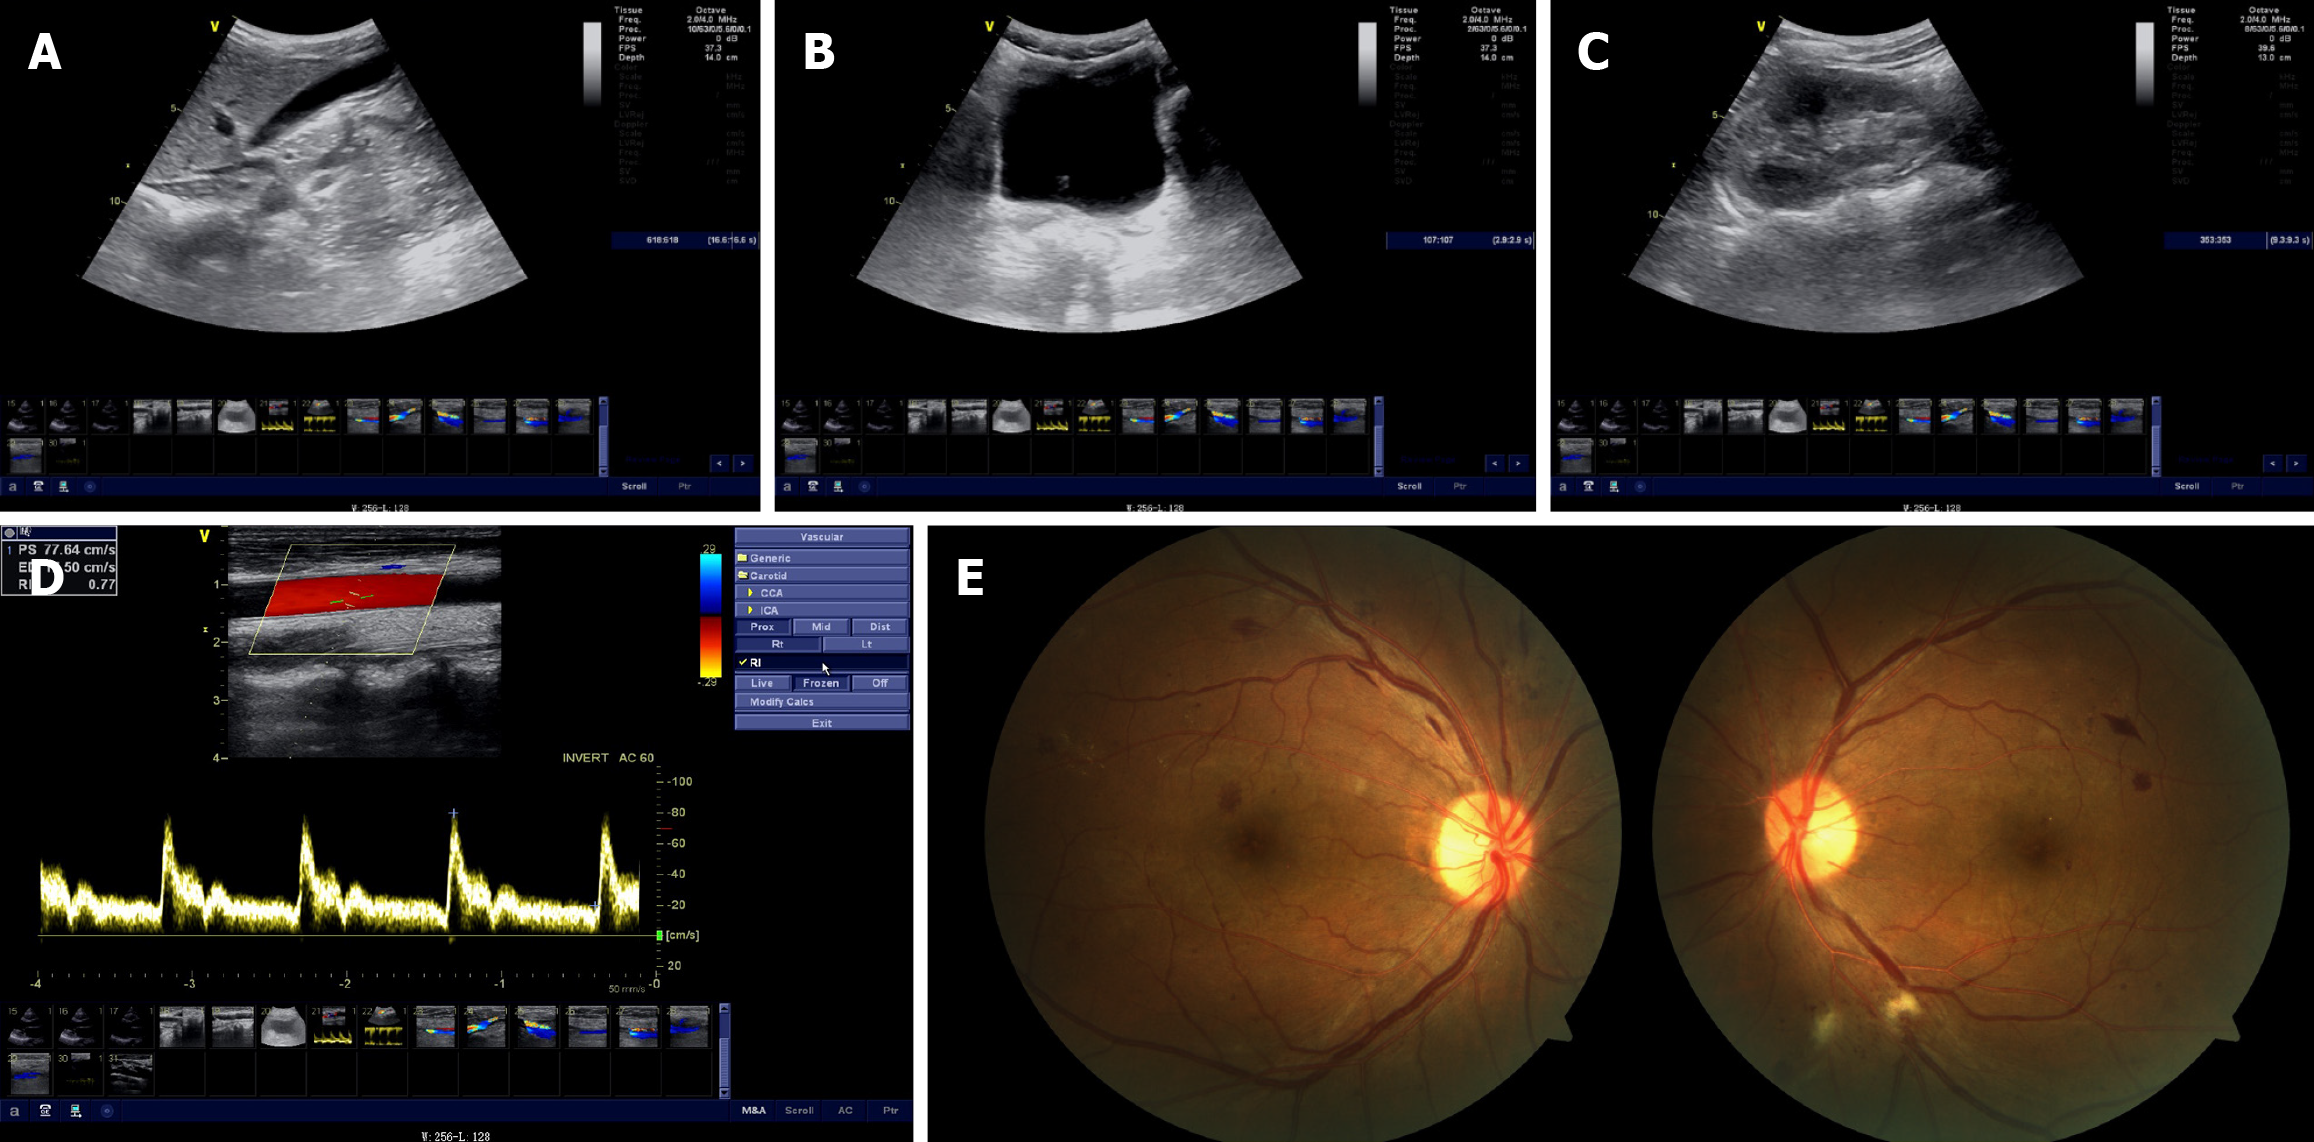

Figure 1 Imaging examinations and fundus photography of the proband.

A: Ultrasonogram of the urinary system; B and C: Abdominal Doppler ultrasound; D: Cervical Doppler ultrasound; E: Fundus photography.